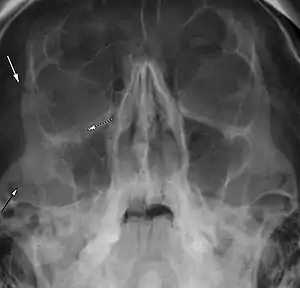

Right zygomaticomaxillary complex fracture with disruption of the lateral orbital wall, orbital floor, zygomatic arch and maxillary sinus.